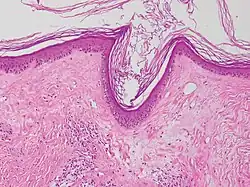

| Lichen sclerosus | Hyperkeratosis, atrophic epidermis, sclerosis of dermis and dermal lymphocytes.[3] |

| ||